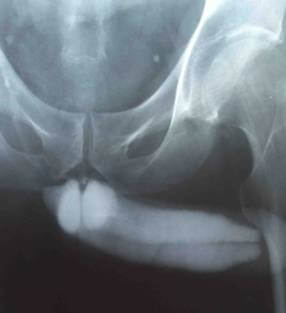

Исследование применяют в сложных случаях. Оно позволяет отличить венозную окклюзию и недостаточность артериального притока, а также определить место сброса венозной крови в артериальное русло пениса.

- выявить патологический венозный отток при веногенной эректильной дисфункции;

- оценить структурные изменения пещеристых тел, а также выявить наличие в них очагов атрофии и склероза. Выявить бляшки при болезни Пейрони;

- выявить места разрыва в кавернозном теле, которые возникли вследствие травм полового члена.

Перед выполнением процедуры в пенис могут вводить 10 мкг простагландина Е1 для индукции эрекции. Если спустя четверть часа после введения препарата у пациента не возникает эрекция – это указывает на наличие органической эректильной дисфункции.